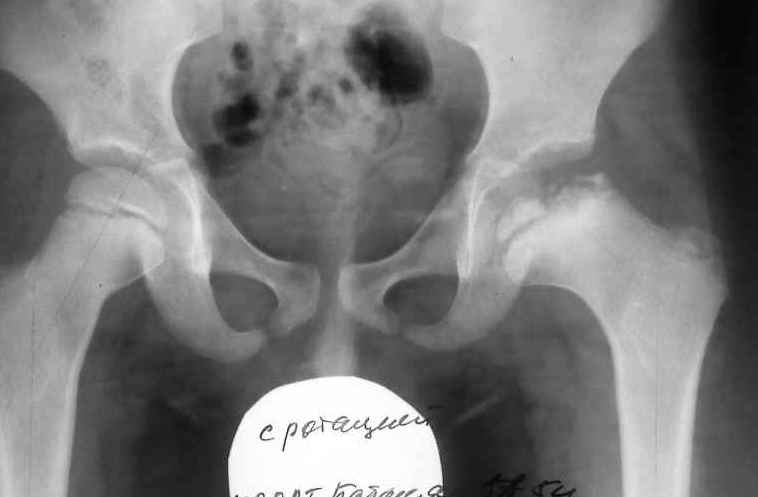

Вначале болезни диагноз поставить тяжело, поскольку симптоматика размыта. Начиная со второй стадии признаки недуга четко видны на рентгенологическом снимке.

Однако рентгенологические признаки в виде расширения щели сустава, очагов деструкции субхондральной пластинки головки бедренной кости появляются слишком поздно, когда у пациентов практически исчезает болевой синдром, а хромота нарастает. На этой стадии пациенты нуждаются в проведении оперативного лечения [6].

Диагностика болезни Пертеса прежде всего проводится с помощью рентгена. При этом точно определяются стадии деформации недуга.

Фото выполняется сразу в нескольких проекциях, чтобы ортопед мог подробно все рассмотреть. Для подтверждения диагноза назначается УЗИ, томография и артроскопия.